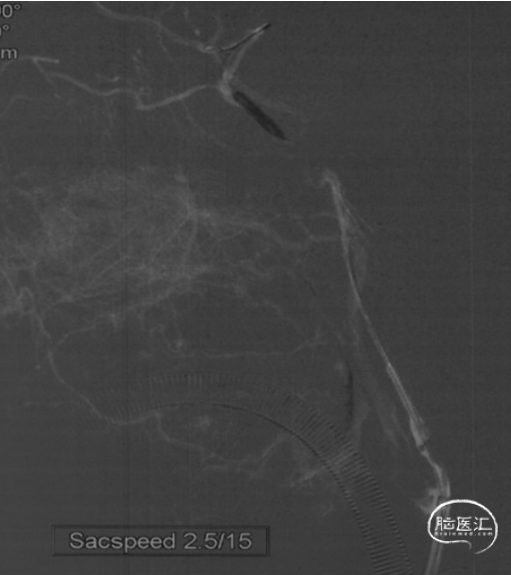

璞慧微导丝技术送至M1段,撤出微导管送入Sacspeed 2.5/15:Sacspeed 2.5mm/15mm球囊自远及近扩张

将Syphonet 4*30支架释远端放在M1段,建立远端保护

3*12 NC-trek支架内扩张

拟将抽吸导管越过Apollo支架至血栓近端,但多次尝试CAT7均无法通过支架。后予2/12 NC-trek球囊部分充盈,辅助CAT7通过Apollo支架到达C6段,抽拉结合,取出血栓,随后恢复前向血流。